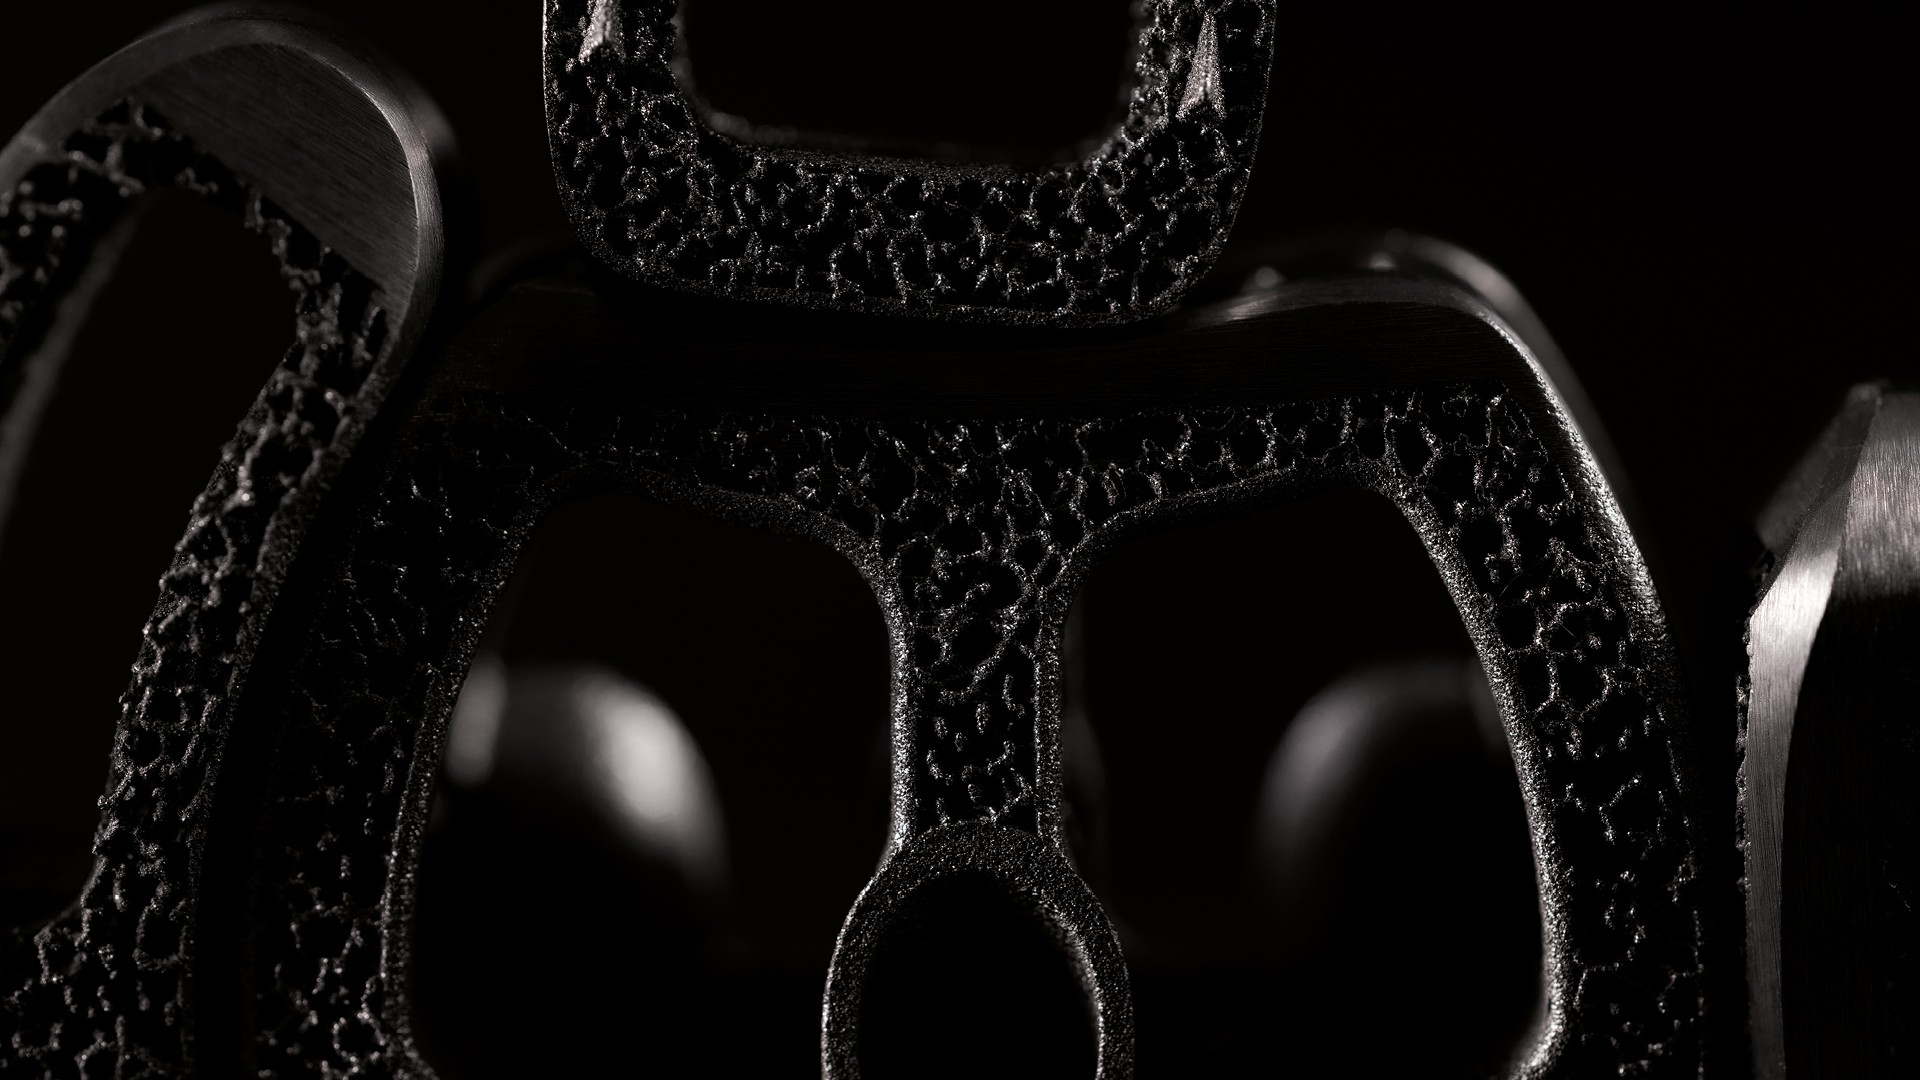

Ti-LIFE Technology

Spineart’s Ti-LIFE Technology enhances additive manufacturing to create a porous titanium structure that mimics natural bone, promoting cell colonization and optimizing medical imaging.

The modulus of elasticity is close to that of natural bone, while the surface properties enhance robust osseointegration compared to PEEK.

Promoting bone ingrowth.